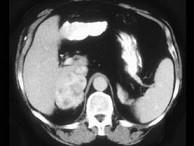

问题 女,32岁,阵发性高血压2年余,请结合所提供图像,作出诊断()

选项 A.左肾上腺腺瘤 B.左肾上腺腺癌 C.左肾上腺转移瘤 D.左肾上腺嗜铬细胞瘤 E.左肾上腺淋巴瘤

答案 D